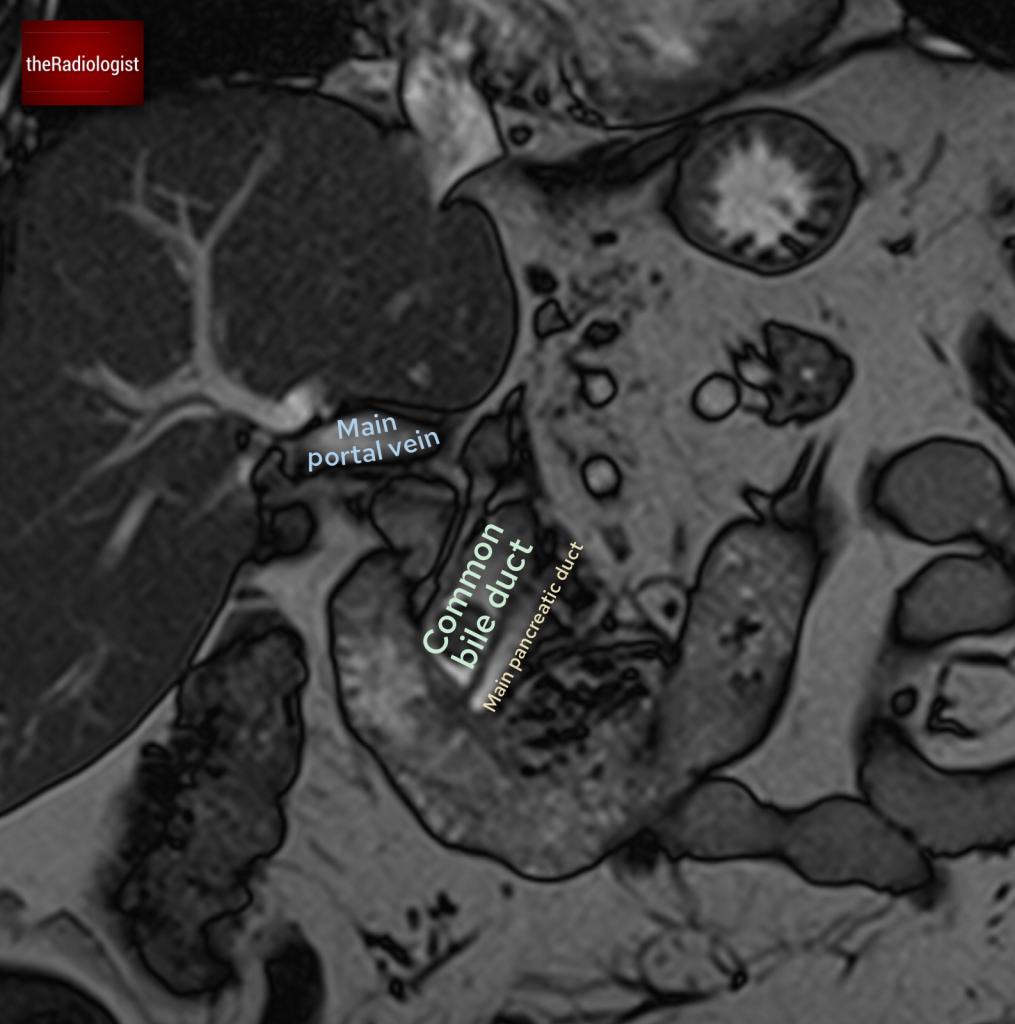

Although we couldn’t see this on our CT case, irregularity of the endplates can be seen after a few weeks on X-Ray and CT as well as loss of disc space. MRI is more sensitive and we are looking for high T2 or STIR signal within the endplates, disc and paraspinal tissues and psoas muscles. Gadolinium contrast can help as we may see enhancement of the endplates, disc and peripheral enhancement of any abscesses. It’s important on MRI to ensure there is no significant central canal stenosis secondary to abscess formation or vertebral collapse.